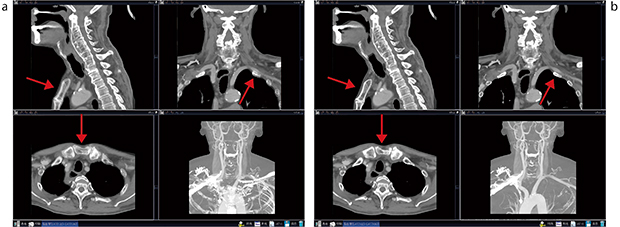

頸部頸動脈内膜剥離術(carotid endarterectomy:CEA)やステント留置による経皮的頸部頸動脈形成術(carotid artery stenting:CAS)前後の評価を行うために,頸動脈CTAも積極的にサブトラクションを行うようにしている。大動脈弓から頭部までを撮影することが多く,以前は呼吸の動きによる胸郭や咽頭などのミスレジストレーションにより,精度の高いサブトラクションができていなかった。更新後は高度な非剛体レジストレーション技術が搭載されたことで,呼吸の動きによる位置ズレを補正し,高精度なサブトラクション画像を得ることができるようなった。そのため骨除去などの作業が軽減され,画像作成時間が短縮している(図3)。

図3 頸部CTAサブトラクション

a:従来法

b:非剛体レジストレーション。肋骨・胸骨がサブトラクションされている。→部分が補正されている。